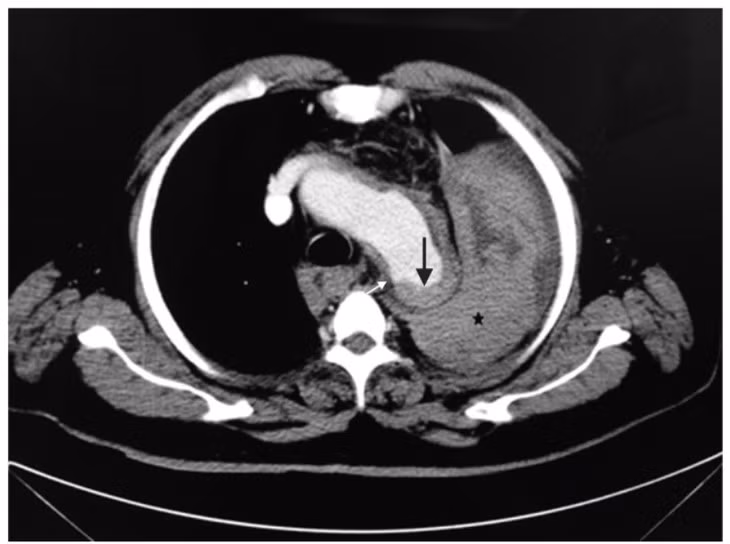

Ngày hôm sau, bệnh nhân bất ngờ hôn mê sau khi hắt hơi. Bác sĩ kiểm tra qua chụp CT xác định vỡ túi phình động mạch chủ khiến người bệnh shock và tử vong ngay sau đó.

| Kết quả chụp CT cho thấy bệnh nhân bị vỡ phình động mạch chủ. Ảnh BSCC |